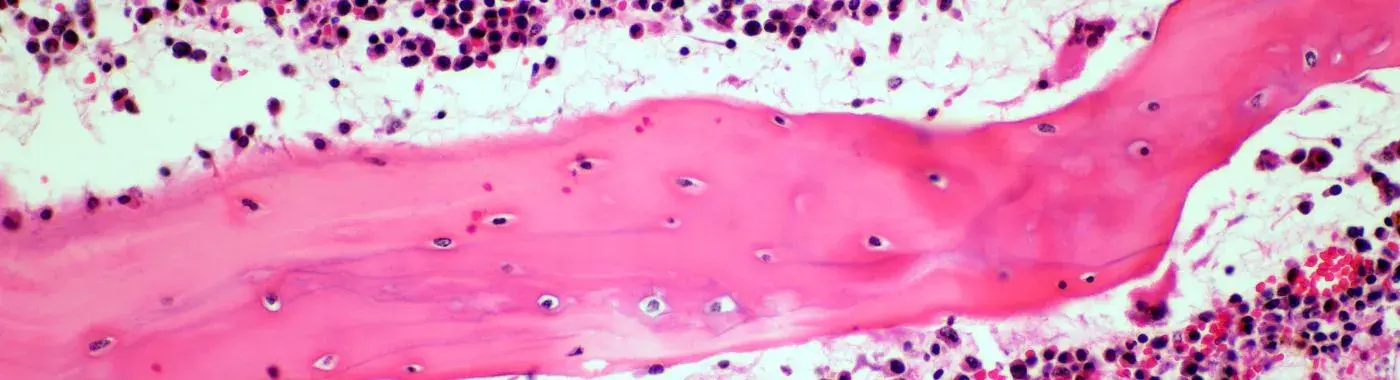

Adenoid Cystic Carcinoma is a type of cancer that originates from the glandular tissues, particularly the salivary glands. It is classified as a salivary gland tumor and is known for its unique histological features, which include a mix of tubular and cribriform patterns. ACC is often considered a low-grade malignancy due to its slow growth; however, it can be aggressive in its local invasion and has a propensity for distant metastasis, particularly to the lungs and bones.